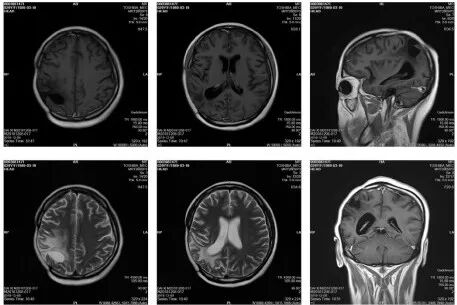

图1. 第一次术前MRI图像(2017.1.11)

图2. 第一次术后颅脑MRI图像(2017.1.22)